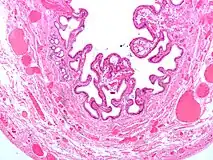

Micrograph of cholesterolosis of the gallbladder, with an annotated foam cell. H&E stain.

The name strawberry gallbladder comes from the typically stippled appearance of the mucosal surface on gross examination, which resembles a strawberry. Cholesterolosis results from abnormal deposits of cholesterol esters in macrophages within the lamina propria (foam cells) and in mucosal epithelium. The gallbladder may be affected in a patchy localized form or in a diffuse form. The diffuse form macroscopically appears as a bright red mucosa with yellow mottling (due to lipid), hence the term strawberry gallbladder. It is not tied to cholelithiasis (gallstones) or cholecystitis (inflammation of the gallbladder).[2]